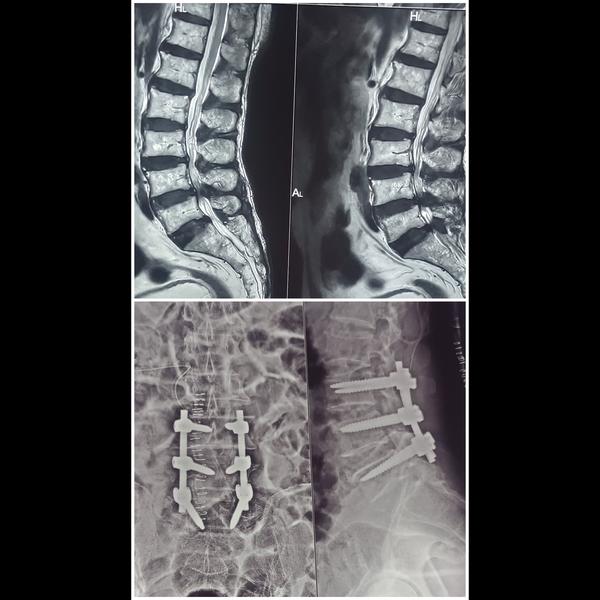

MICROSCOPIC SUCCESSFUL SPINE SURGERY

View Details30-YEAR-OLD PATIENT WITH SEVERE LOW BACK PAIN, UNABLE TO WALK. MRI SHOWED L5 PARS INTER-ARTICULARIS...

L3-L4, L4-L5 DISC PROLAPSE, SEVERE SPINAL CANAL STENOSIS –SPINAL FIXATION & DECOMPRESSION DISCECTOMY